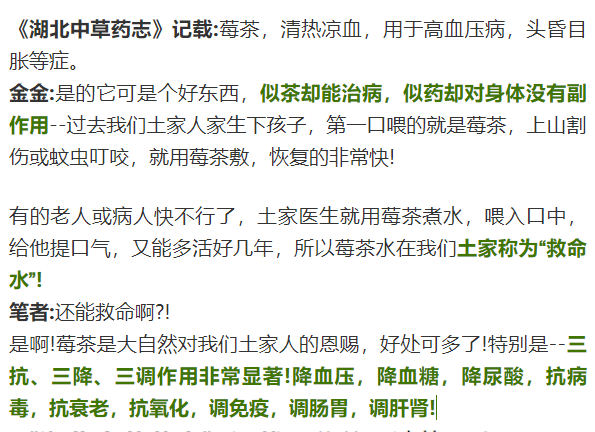

02 | 张家界土家莓茶九大功效作用 |

03 | 张家界特有莓茶 |

张家界茅岩河地处云贵高原东端、武陵山脉腹地,山高谷深,森林茂密,常年温暖湿润、云雾缭绕。特别是茅岩河红砂岩分布的地区,很难适合其它农作物的生长,但这却为莓茶生长提供了得天独厚的条件。土家富硒莓茶就生长于此!

除此之外,土家莓茶对夜生活过度、烟酒过量、口干、舌燥、口苦乏力、神疲心烦的人,特别好!最令人惊讶的是——张家界人民医院把土家莓茶用于新肺炎病毒的防控!